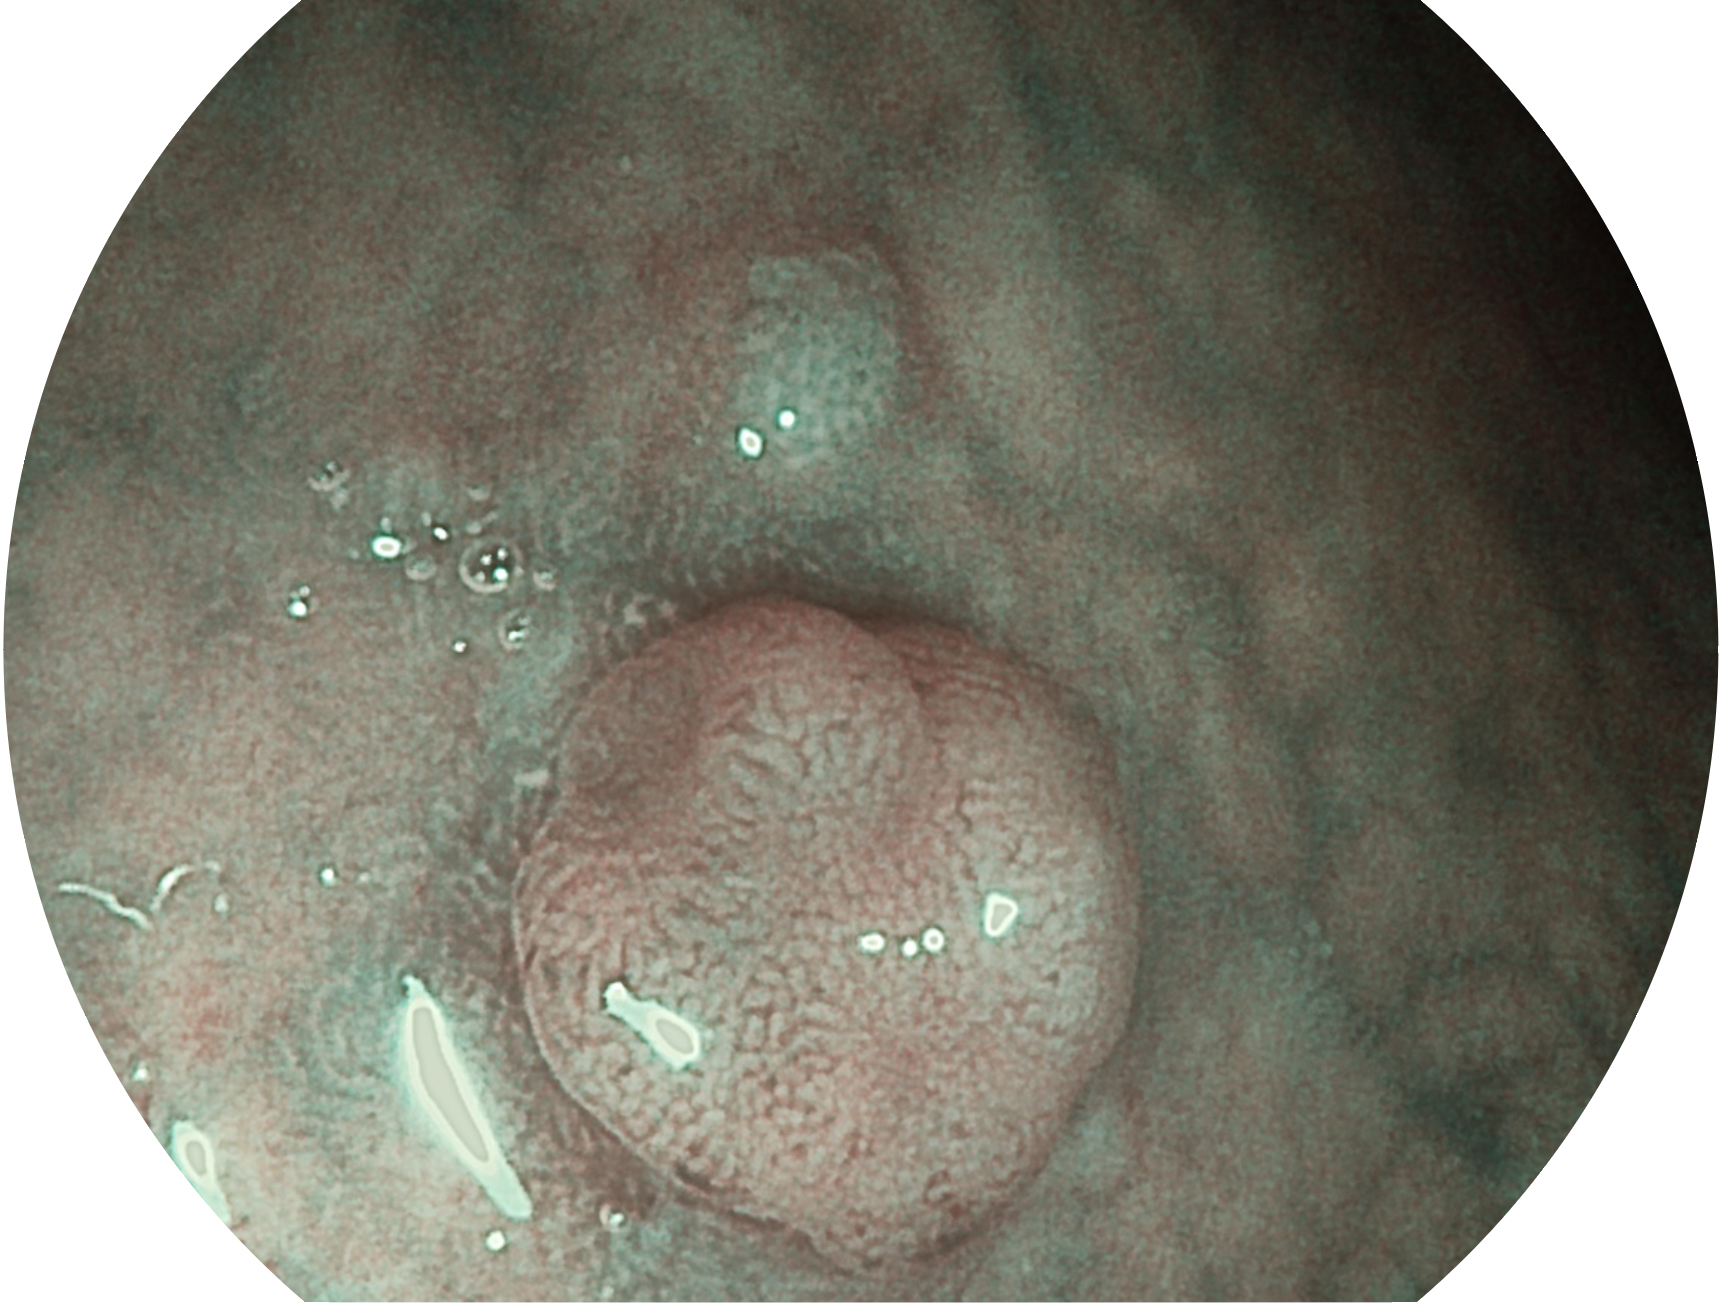

db真人体育官网新开发的内镜染色技术,主要是基于多波长LED 光源的开发,VLS-55Q 四波长LED 光源是由四个不同颜色的LED光按照相应照明模式所规定的特定发光比例进行合束后形成,合束后形成的照明光的光谱由红光、绿光、蓝光及蓝紫光这四个不同的波段范围构成。具有更高光谱自由度,通过光谱比例的控制,实现了聚谱成像技术,英文全称为“Spectral Focused Imaging, SFI”,缩写为“SFI”和光电复合染色成像技术,英文全称为“Versatile Intelligent Staining Technology, VIST”,缩写为“VIST”。